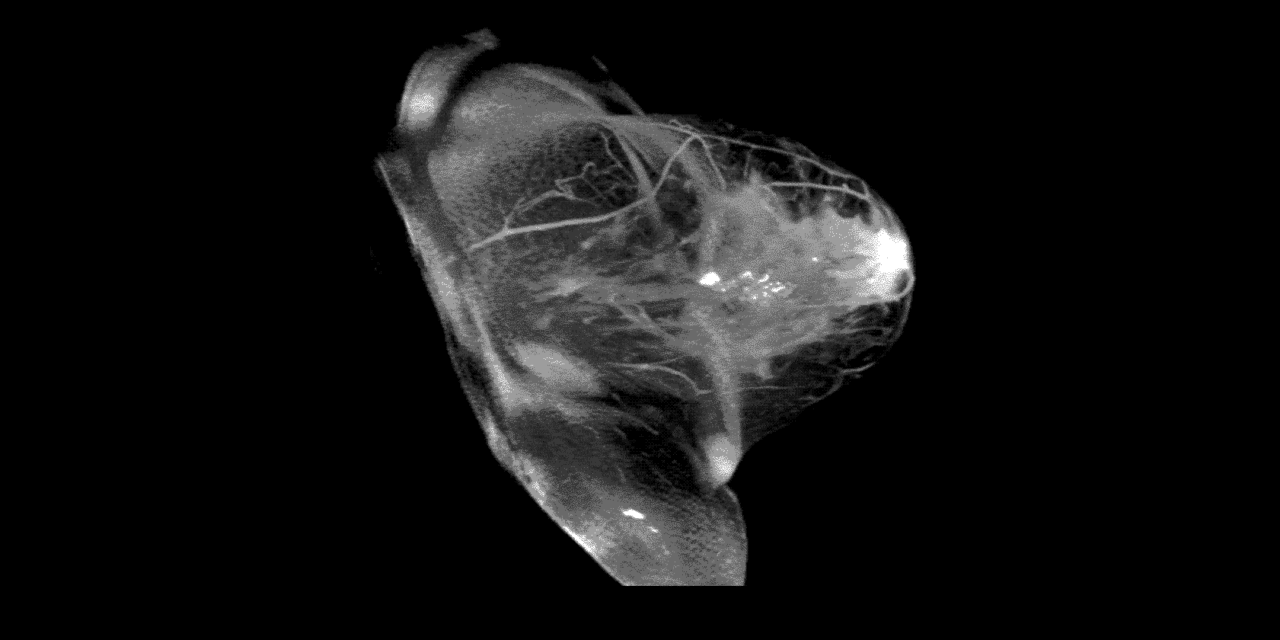

Breast Health Imaging